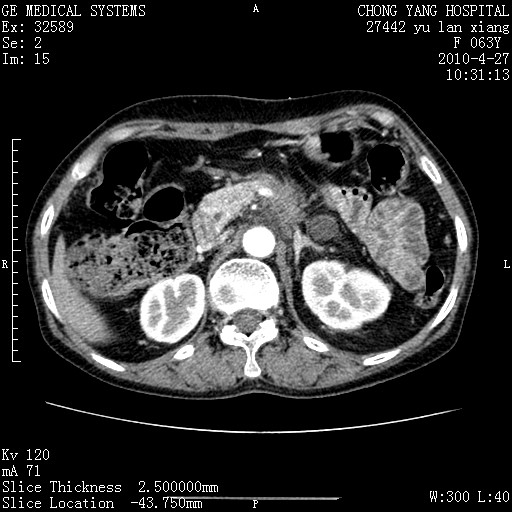

标题: CT26066:F63Y 上腹正中压痛半月,CA199:7400u/ml,MR示胰腺炎伴 [打印本页]

胰腺癌侵犯腹腔动脉干-分支、胃壁、左侧膈肌伴胰周及腹膜后淋巴结转移、胆囊切除术后。

胰腺癌侵犯腹腔动脉干-分支、胃壁、左侧膈肌伴胰周及腹膜后淋巴结转移、胆囊未显影。